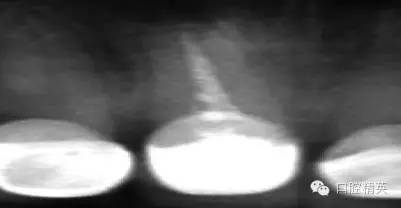

關(guān)于基礎(chǔ)治療。牙周治療和根管治療是美觀修復(fù)的基礎(chǔ)。根據(jù)術(shù)前檢查,常規(guī)先行全口潔治,必要時(shí)局部深層次的牙周治療,待牙周情況穩(wěn)定后,再考慮牙體預(yù)備與取模(見圖1、2)。在牙周炎未控制或牙齦紅腫的情況下,是不可能預(yù)備好牙齒,不可能取得清晰的印模,更談不上成功的美觀修復(fù)。

根管治療更是牙體修復(fù)的基礎(chǔ),根據(jù)術(shù)前診斷,對需要做根管治療的或有必要重新做根管治療的,一定要做到恰充,消除隱患,避免將來冠修復(fù)好后,出現(xiàn)根尖炎癥的問題(見圖3、4、5)。在基礎(chǔ)工作做好后,接下來開始牙體預(yù)備,根據(jù)跟個(gè)人習(xí)慣,選擇合適的車針(圖6、7)。